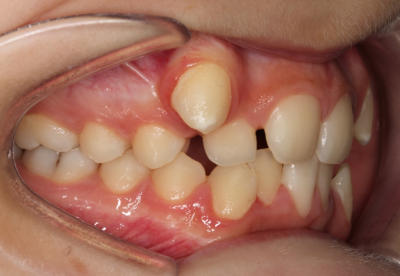

Crowding – Child case